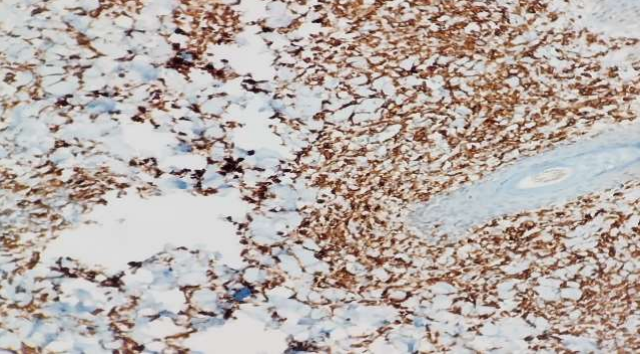

A skin biopsy revealed an interstitial infiltration of atypical cells without epidermotropism in the dermis and subcutaneous tissues. The tumour cells had ill-defined borders, moderate to abundant cytoplasm and oval, elongated or cleaved nuclei with occasional nucleoli with pale to hyperchromatic chromatin. The background consisted of some T cells and scattered small lymphocytes. (Fig 2) Immunohistochemistry, the atypical cells showed positive staining for leukocyte common antigen (LCA), CD30, CD68, and CD4 (Fig   3,4) while negative for CD20, CD45, MPO, CD34, CD117, ALK, PAX-5, AND CK; Ki-67 – 70-80%. (Fig 5) The final diagnoses considered were Lymphamatoid Papulosis Type C or small cell variant of ALCL.[5]A final diagnosis of LyP type C was made based on the waxing and waning course of the disease. Further evaluations including a complete hemogram, chest radiograph, and ultra-sound of the abdomen which did not reveal any abnormality. After careful counselling, patient was asked to be in close observation and steroid cream for local application. Patient was instructed to report she developed any of the following:

Figure 1, 2, 3, 4

Figure 3

Figure 4